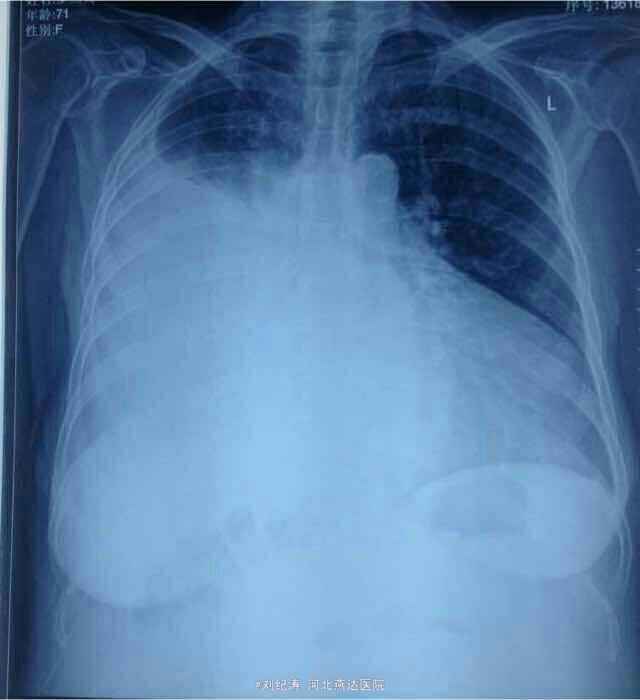

查体:心率78次/分,血压104/72mmHg,端坐体位,双侧胸廓对称,右肺语颤增强,右肺呼吸音弱,左肺呼吸音正常,心律齐,腹部膨隆,腹水征阳性,移动性浊音阳性,双下肢轻度凹陷性水肿。 辅助检查: 胸片:1、右侧胸腔积液,2、左心室增大(有心衰影像表现)。心脏彩超:EF21%,全心扩大,二尖瓣关闭不全,三尖瓣关闭不全(中度)并肺动脉高压,心功能减低。 腹部彩超:肝脾双肾未见明显异常,胰腺显示不清,腹腔积液(深约11cm)。 妇科彩超:未见明显异常。 肿瘤标志物:CA199:91.58U/ml,CA125:>400U/ml. 胸腹水脱落细胞学检查未见癌细胞。

拟诊:1、扩张性心肌病 二、三尖瓣关闭不全 慢性心功能衰竭 2、右侧胸腔积液 3、腹腔积液(肿瘤不除外) 治疗:入院后完善检查,考虑心源性所致,给予胸腹腔穿刺置管流胸腹水(交叉放水),强心利尿、抗炎、扩管、纠正心衰及对症治疗一周,腹水明显减少,胸水未见明显减少,此时肿瘤标志物回示:CA125、CA199升高,遂行妇科彩超排除妇科肿瘤,结果未见异常,欲行CT进一步检查,患者家属未接受;继续引流胸水及对症治疗3天,患者腹胀、气喘症状明显好转,胸腔积液较前减少,欲行胸部CT进一步检查,患者未接受,切见症状好转,要求出院,反复劝说无效后予以出院。出院继续口服强心利尿药物。

随访:患者20天后门诊复查彩超:右侧胸腔积液深约5cm,腹腔少量积液;患者无胸闷、气喘、腹胀不适。 讨论:在诊断方面,首要考虑心源性,其次是肿瘤性,肿瘤标致物不是特异指标,CA125增高可见于卵巢癌,浆膜腔恶性积液,淋巴瘤,盆腔炎症,CA199升高有胰腺癌,胰腺炎,其他消化道肿瘤等。肿标的持续升高对诊断肿瘤意义更大。 肺癌继发恶性腹水的临床上真心罕见,反倒是消化道、卵巢恶性肿瘤继发恶性胸水的多见。 左心衰或者全心衰竭可以仅仅出现单侧胸腔积液,并且可以是大量的,甚至是血性的,此外心衰引起的胸腔积液有个特点,就是如果是单侧,右侧多见,如果是双侧的话,右侧积液量多于左侧,关于这个特点,文献里有报道,大家可以查一下,解释的原因较多。而这个患者的胸腔积液就在右侧,在排除右侧有肺炎,肿瘤等可引起胸腔积液的其他疾病后,首先就要考虑心衰所致,患者胸片心影明显增大,最重要的是心脏彩超汇报全心扩大,射血分数21%,扩张性心肌病等,因此诊断心力衰竭应该没有问题!心力衰竭,特别是全心衰竭引起胸腹腔积液是可以的。对于心衰引起的这么大的胸腔积液,有时候易被误诊误诊,患者胸腔积液消失慢,如果是心衰所致,那么真正的治疗方法就应该是强心利尿扩血管等,并且用量用药方面有时候要个体话,否则胸腔积液即使抽了还会长,因为本质原因心衰没有得到纠正。 对于该患者胸腹水病因:心源性?肿瘤性?或者其他?您有什么看法?